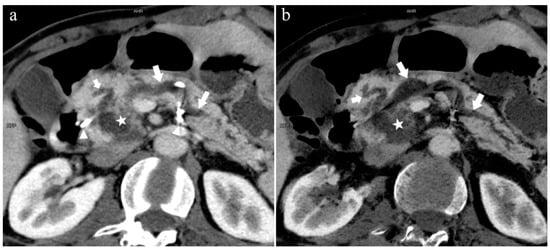

Figure 9.

Type 3a. A 49-year-old male patient with IPMN. (a): MIP [45 keV MEI (+)] shows the enlarged head of the pancreas with tumor (pentagram), and tortuous dilation of MPD (long arrow) and APD (short arrow). The APD communicates with the front segment of the MPD without flowing into the MiP. The drainage tube (arrow) can be seen in the MPD. (b): MinIP [45 keV MEI (+)] reduces the interference of ductal artifacts and shows the course and more detail of the distal pancreatic duct. Postoperative pathology confirmed that the mass was IPMN.

Figure 10.

Type 2b. A 45-year-old female patient with Cholangitis. (a): MIP [45 keV MEI (+)] shows MPD (long arrow) flows into MiP and extends to the tail of the pancreas. The tiny APD (short arrow) communicates with the front segment of the MPD without flowing into the MP. (b): MinIP [45 keV MEI (+)] shows the overall configuration of the pancreatic duct and the thin duct in the tail. MPD refers to anatomically large and functionally dominant ducts.